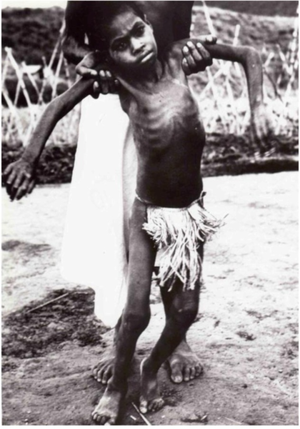

В 1949 году в Тарибо (область Кейагана) была организована первая лютеранская миссия, а вскоре и первый патрульный пост, созданный специально для прекращения междоусобицы и поддержания порядка. Первый патрульный офицер района Джон МакАртур 6 декабря 1953 года, проходя к деревне Амуси, увидел сидящую у костра маленькую девочку. Джон МакАртур писал в своём дневнике:

|

«Она сильно дрожала, а голова её покачивалась из стороны в сторону. Мне сказали, что она жертва колдовства и что эта дрожь продолжится вплоть до её смерти. До самой смерти она не сможет есть. Через несколько недель она должна погибнуть».[1] |

ходить или сидеть прямо без посторонней

помощи и серьезно не доедает.

Источник: https://ru.abcdef.wiki/wiki/Kuru_(disease)

Джон МакАртур продолжал встречать среди туземцев подобные случаи заболевания, которое, как он вскоре установил, называлось «куру» ˗˗ словом, означающим у папуасов Новой Гвинеи дрожание от холода или от страха. Более того он оказался достаточно проницательным человеком, предположив, что куру – новое, неизвестное в то время заболевание человека. Эти данные, в виде короткого сообщения получил Австралийский врач прибалтийского происхождения Винсент Зигас. В результате с 1959 года он начал наблюдения над больными аборигенами. В октябре того же года Зигас провёл несколько недель в области Окапа, где собрал сыворотки крови у двадцати шести больных куру и даже сумел взять некроптаты мозга человека, умершего от этого заболевания. Но первые попытки лабораторного исследования заболевания не внесли ясности в природу куру.